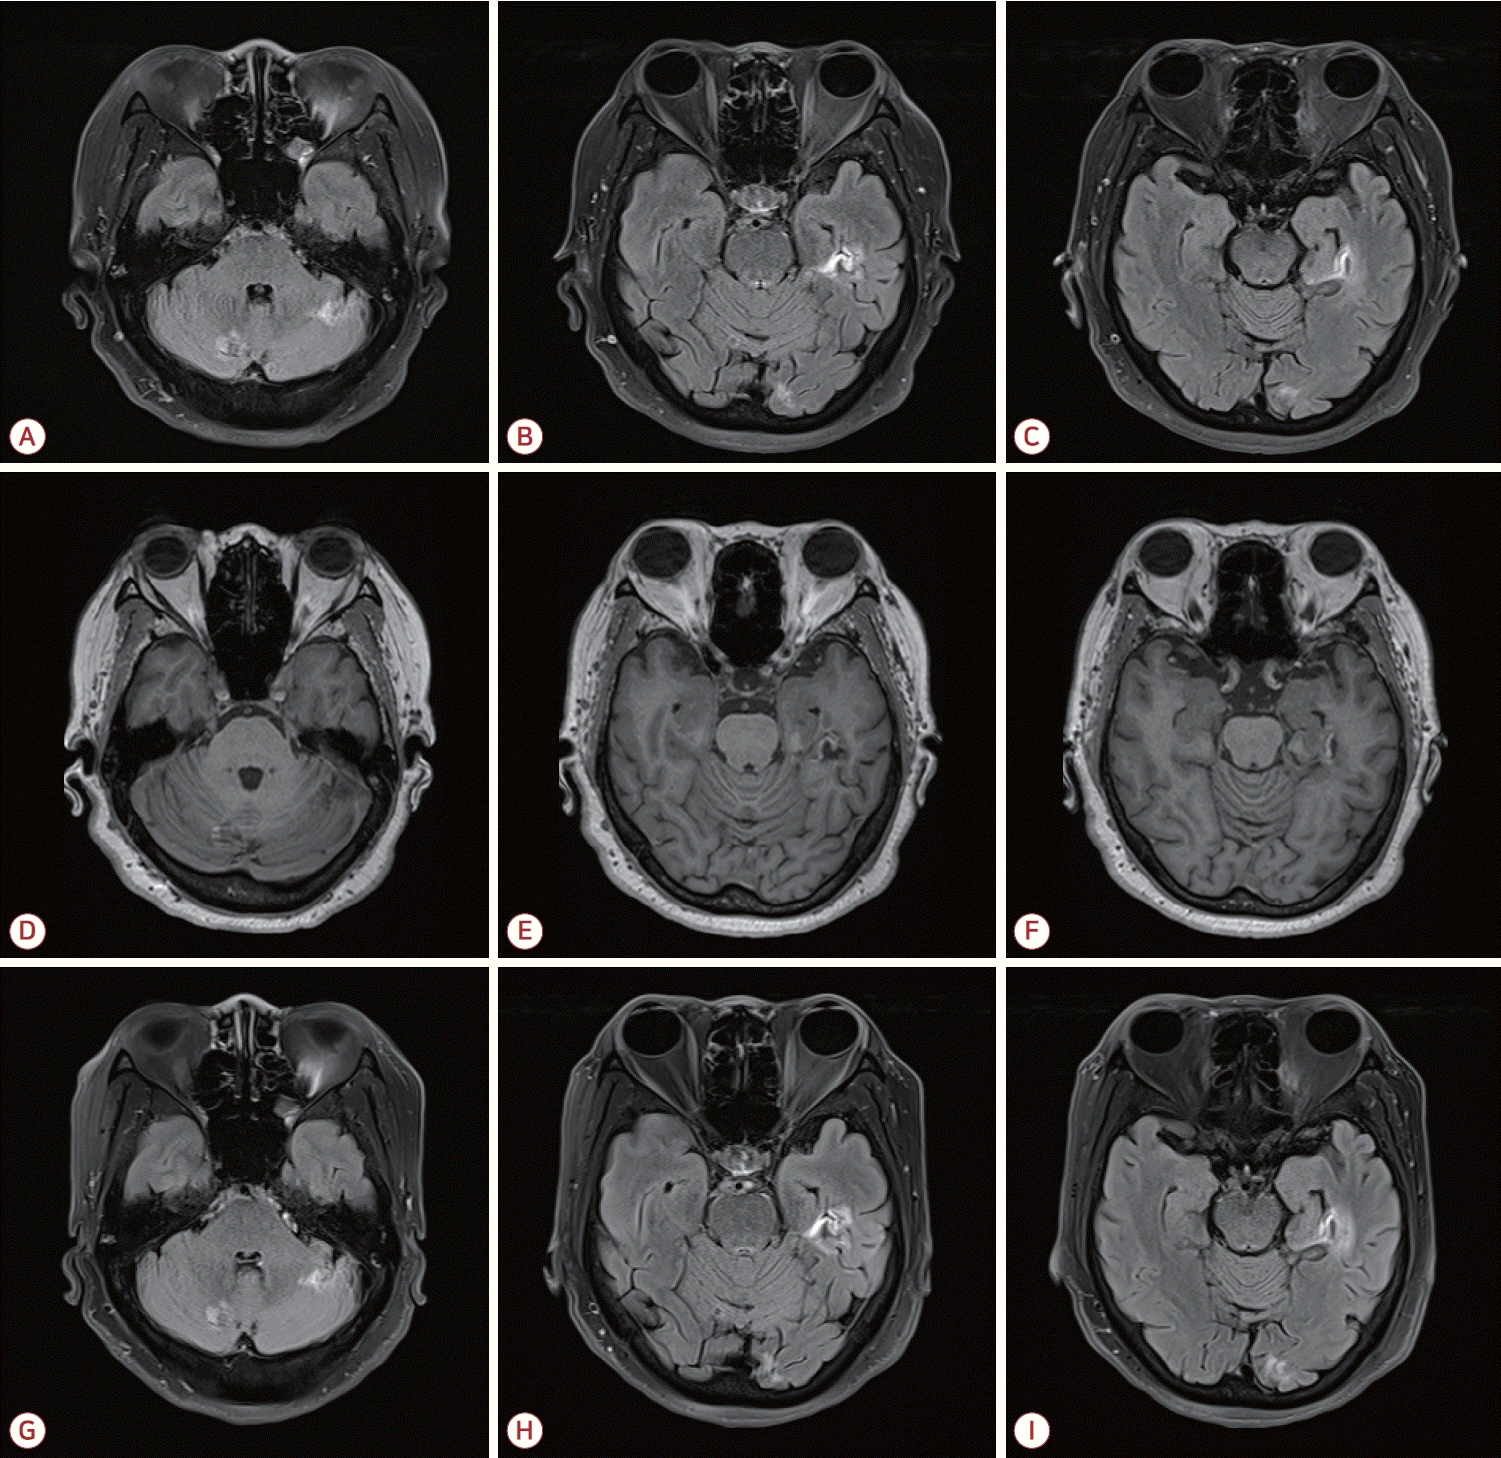

Figure 1.

Brain MRI performed prior to the diagnosis of MPO-ANCA-associated vasculitis demonstrates no abnormal signal on FLAIR images (A-C) or T1-weighted images (D-F). Magnetic resonance angiography (MRA) reveals no significant stenosis or vascular abnormality on carotid MRA (G) or intracranial MRA (H-I). MRI; magnetic resonance imaging, MPO; myeloperoxidase, ANCA; antineutrophil cytoplasmic antibody, FLAIR; fluid attenuated inversion recovery.